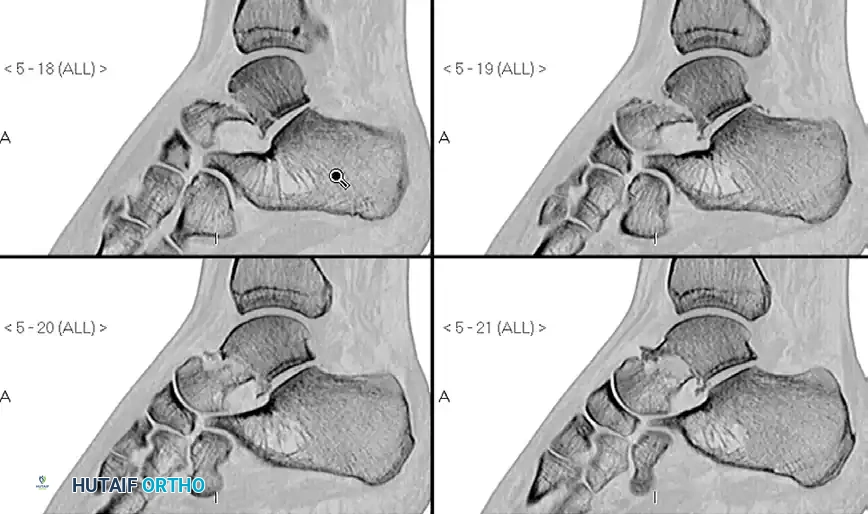

Surgical Warning: A talar neck fracture must be thoroughly evaluated before labeling it as a Type I. Many fractures, if examined closely by CT scans, display subtle displacement. If any doubt exists about the presence of displacement, a fine-cut CT scan with sagittal and coronal reconstructions is mandatory.

Pre-operative Imaging (Talar Neck Fracture):

Pre-operative Imaging (Comminuted Talar Neck Fracture):